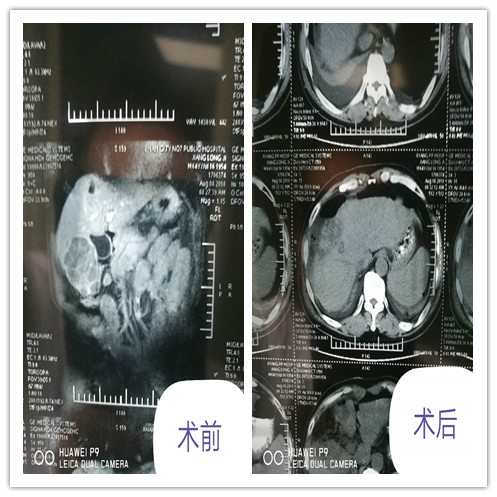

近日,我院普外科成功治愈大肝癌一例,现患者恢复良好,正在进一步康复中。

患者肝脏肿瘤大,且多发,加之肿瘤位置深、合并乙肝大三阳肝功代偿差,手术治疗风险极高,吴主任积极组织科室骨干医师进行病例讨论,制定详尽的手术方案。普外一科医护人员积极完善术前准备,评估患者的肝、肺、心功能,于8月11日由吴德顺副主任医师、付磊主治医师、王洪序主治医师、温庆彬住院医师为其行肝癌根治术,手术顺利,术后病理结果示:肝右前下叶结节型高-中分化肝细胞肝癌(最大截面积7x5.5cm)手术断端未查见癌组织。目前患者已间断拆线,恢复良好。